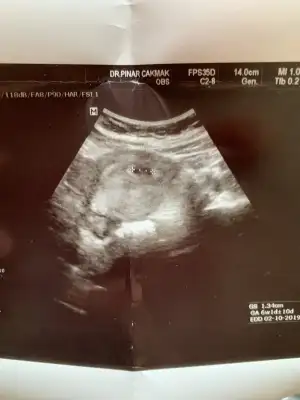

Canim merhaba benim ultrason fotograflarima da bakabilir misin cinsiyet tahmini icin merak ediyorum. 3u de vajinal ultrason 5-6-9.haftalarda

• DFE54A07-7552-444D-8D18-02F085A4ECCE.webp

DFE54A07-7552-444D-8D18-02F085A4ECCE.webp

49,2 KB · Görüntüleme: 90